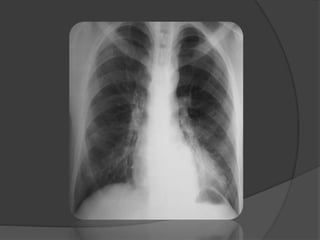

Imagerie: Radiographie du thorax

 Si DAN+ ou signes respiratoires

 Diagnostic positif

 Aspects ≠ type MAKP

 Image kystique inhomogène ou hydro-aérique

 Opacité pulmonaire

 Déviation du médiastin

 Nouveau-né:

 Opacité initialement simple

 Apparition secondaire de formations kystiques

 Radiographie normale ≠ diagnostic si DAN +